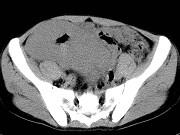

- 单项选择题男,23岁, 下腹部肿块伴持续性钝痛1月余,影像所见如图, 最可能的诊断为 ( )

A、小肠癌

B、小肠淋巴瘤

C、小肠转移瘤

D、小肠结核

E、小肠间质瘤